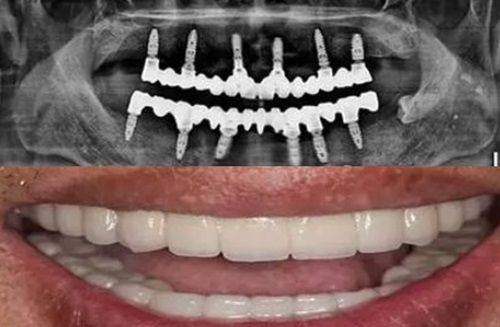

除了专精的医生团队,天津联合丽格医疗美容医院口腔科还引进了一系列精良的牙科设备。这些设备具有高精度、效率高率的特点,能够为牙齿治疗提供更正确的诊断和更有效的治疗。例如,口腔CT能够清晰地显示牙齿的内部结构,帮助医生更好地制定治疗方案;激光治疗设备可以减少治疗过程中的疼痛和出血,提高治疗成效。精良的设备不仅提高了治疗的质量,还缩短了治疗的时间,让患者能够更快地修复健康。